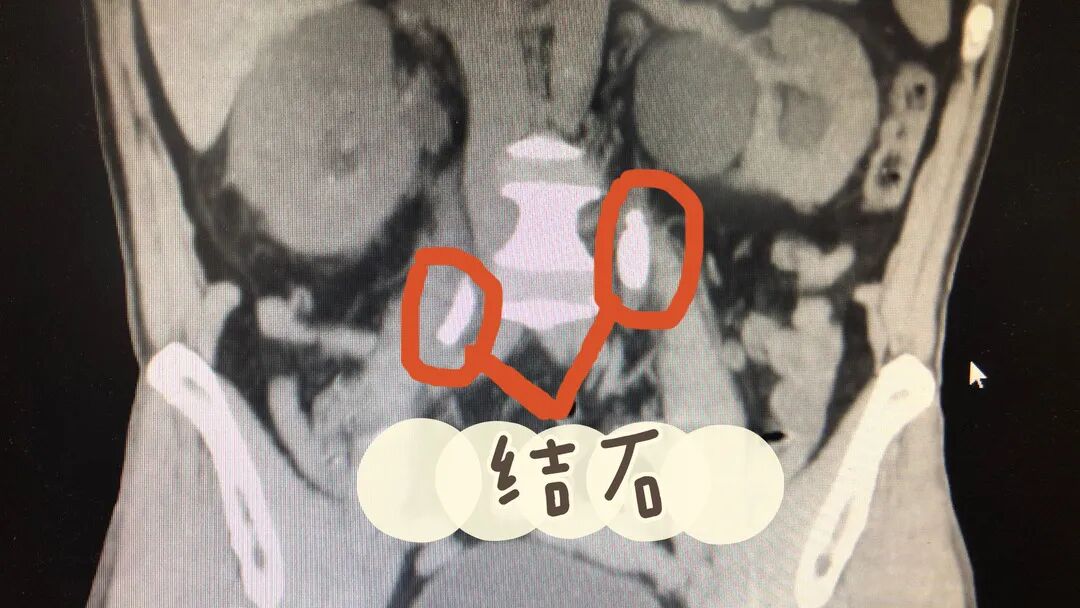

医生查看情况后,安排他做了一系列相关检查,其中泌尿系CT结果提示双肾多发结石,双侧输尿管结石伴尿路扩张积水,肌酐指标达962μmoI/L,超过正常指标近10倍。

图|患者左右两侧输尿管被结石堵住